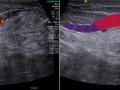

Ginecomastia glandular - ultrassonografia nos modos b, doppler e elastografia

Abscesso mamário

Papiloma intraductal

Elastografia de tumor multifocal da mama

Mastopatia diabética

Diagnósticos mamográfico e ultrassonográfico falsos negativos: relato de caso.

Anatomia ultrassonográfica da mama